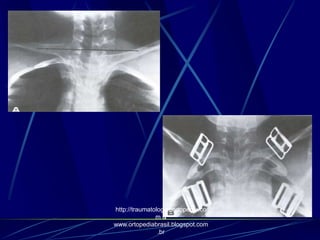

Procedimentos

operatórios:

( A )- Pinos de

Steinmann

( B ) Sutura entre a

clavícula e o

processo coracóide.

( C ) Parafuso de

compressão entre a

processo coracóidehttp://traumatologiaeortopedia.co